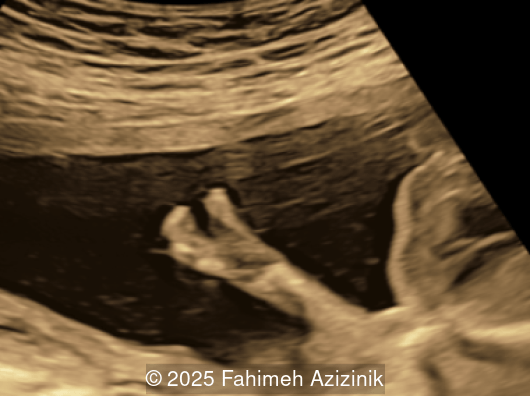

Image 1

• Complex syndactyly of the hands and feet. Complex hand brachysyndactyly with “mitten-like” appearance due to bony fusion of the fingers

Bicoronal synostosis is the characteristic cranial hallmark of Apert syndrome, detectable sonographically from 18 weeks. Its most recognizable manifestation is turribrachycephaly, defined by an elevated cephalic index (typically >85–90%) and a tall cranial vault with marked frontal bossing [19]. On prenatal ultrasound, the face in Apert syndrome shows midface hypoplasia with a depressed nasal bridge, proptosis, hypertelorism, and frontal bossing. The extremities demonstrate syndactyly of both bone and soft tissue of the hands and feet with partial-to-complete fusion often involving second, third, and fourth digits, known as “mitten hands” and “socked feet”. In severe cases, all digits are fused, with the presence of a single nail known as “synonychia” [20]. Other ultrasound findings include mild ventriculomegaly, agenesis of the corpus callosum, deficient or absent septum pellucidum, and fusion of the cervical vertebrae at the level of C5-C6 [21]. Cardiovascular (atrial and ventricular septal defect) and genitourinary anomalies (hydronephrosis, and cryptorchidia) are present in 10% of patients [22]. Increased nuchal translucency in the first trimester [23], widely open metopic suture [24], and polyhydramnios [25] have also been reported. Three-dimensional (3D) ultrasound facilitates assessment of surface abnormalities of the face and extremities, and magnetic resonance imaging (MRI) can be used to evaluate associated intracranial conditions [26].